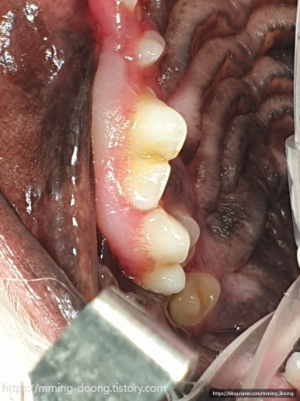

역시..구강캠 진료만으로도 예상보다 훨씬 심각한상태

치석이 심한건 알았지만 저 정도까지일줄은

꿈에도 몰랐다 진짜 사진보고 경악함..ㄷㄷ🫢

아래쪽 어금니 상태가 가장 안좋아서

X-ray 찍어봐야 정확히 알 수 있지만,